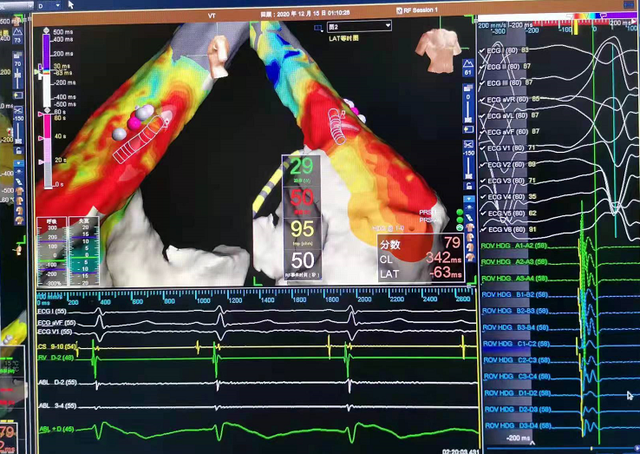

电生理标记三维图

经导管射频消融术是一种微创技术,它通过静脉血管途径将电极导管插入心脏,用电生理标测技术找到心脏内异常电传导通道或异位搏动点向患者病变部位释放射频电流,使局部组织产生凝固性坏死,达到阻断异常传导通道或消灭异位起搏点的目的,让患者心脏恢复正常跳动。